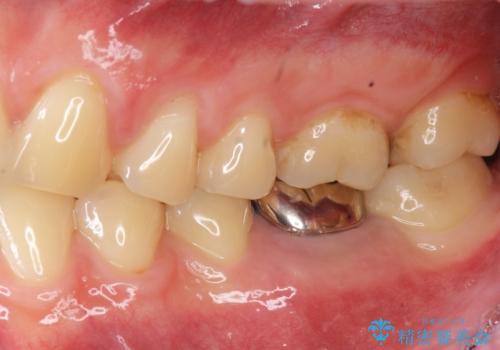

銀歯を除去して見ると内部で虫歯が再発し、歯の辺縁は破折し保存が難しく抜歯をしなければいけない状態でした。

抜歯後ブリッジとインプラント治療を検討・相談し、より周囲の歯を削らずに済むインプラント治療を希望されたのでインプラントによる機能回復を計画します。